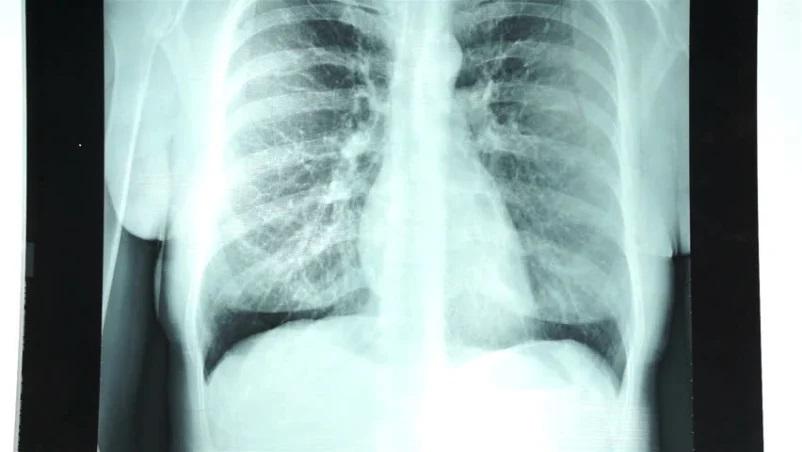

Rontgen dada atau rontgen thorax adalah tes pencitraan melalui foto dada yang menunjukkan jantung, paru-paru, saluran pernapasan, pembuluh darah, dan nodus limfa.

Prosedur ini juga bisa menunjukkan tulang belakang dan dada, termasuk tulang rusuk, tulang selangka, dan bagian atas tulang belakang Anda.

- Hasil rontgen paru-paru terlihat normal dalam ukuran dan bentuk. Jaringan paru pun terlihat normal. Tidak ada pertumbuhan massa dalam paru-paru. Ruang pleura (ruang yang mengelilingi paru-paru) juga terlihat normal.

- Jantung terlihat normal dalam ukuran dan bentuk. Jaringan jantung pun terlihat normal. Pembuluh darah dari dan yang mengarah ke jantung juga normal baik dalam ukuran, bentuk, dan tampilan.

- Tulang termasuk tulang belakang dan rusuk terlihat normal.

- Diafragma terlihat normal dalam bentuk dan letak.

- Tidak terlihat adanya penumpukan cairan atau udara yang abnormal, dan tidak ada benda asing yang terlihat.